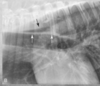

What view is this?

A

left lat

Q

right lat